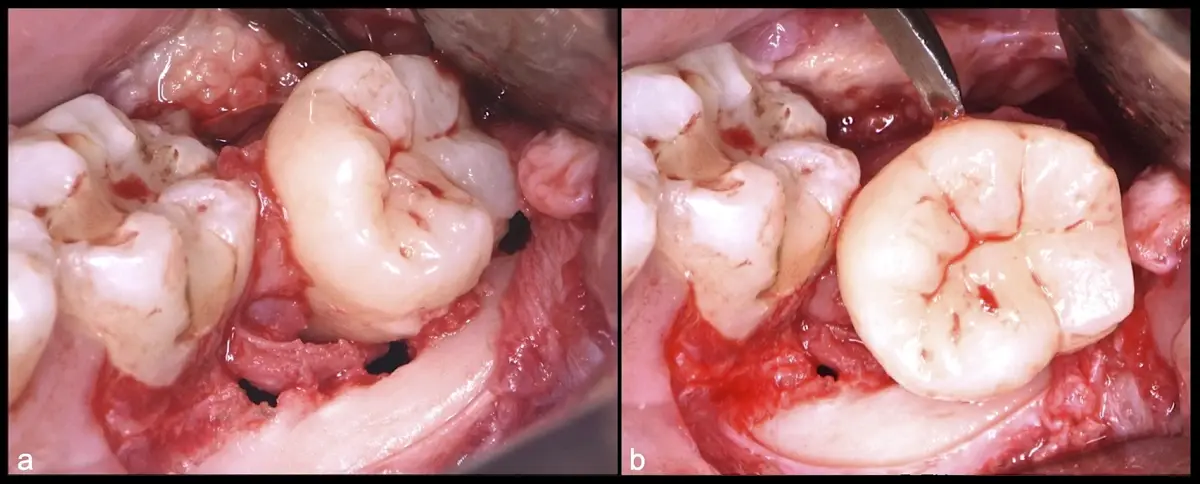

La exodoncia de los terceros molares es uno de los procedimientos quirúrgicos más comunes en odontología y, al igual que con la mayoría de procedimientos orales, debe darse bajo rigurosas evaluaciones clínicas y radiográficas que establezcan previamente un plan de tratamiento apropiado, para reducir y/o evitar la incidencia de cualquier complicación o daño.1

El procedimiento puede variar en su complejidad dependiendo de su ubicación, profundidad, angulación, y la densidad ósea circundante.2 Uno de los pasos más críticos y cruciales en la extracción es la osteotomía previa y concomitante al acceso quirúrgico del diente, para lo cual se utilizan diversos instrumentos como cinceles y martillos, instrumental rotatorio o de corte por ultrasonido.3

Para realizar la técnica de extracción de una tercera molar, una vez que se ha confirmado su diagnóstico, se debe considerar la posición del diente (vertical, mesioangular, distoangular, horizontal u otras), profundidad y grado de impacto, obstrucción a la erupción asociada a la segunda molar, morfología de la raíz (la curvatura de las raíces controla el camino de la exodoncia), relación con el canal del conducto dentario inferior, la patología asociada, la densidad ósea y la Integridad de la segunda molar.